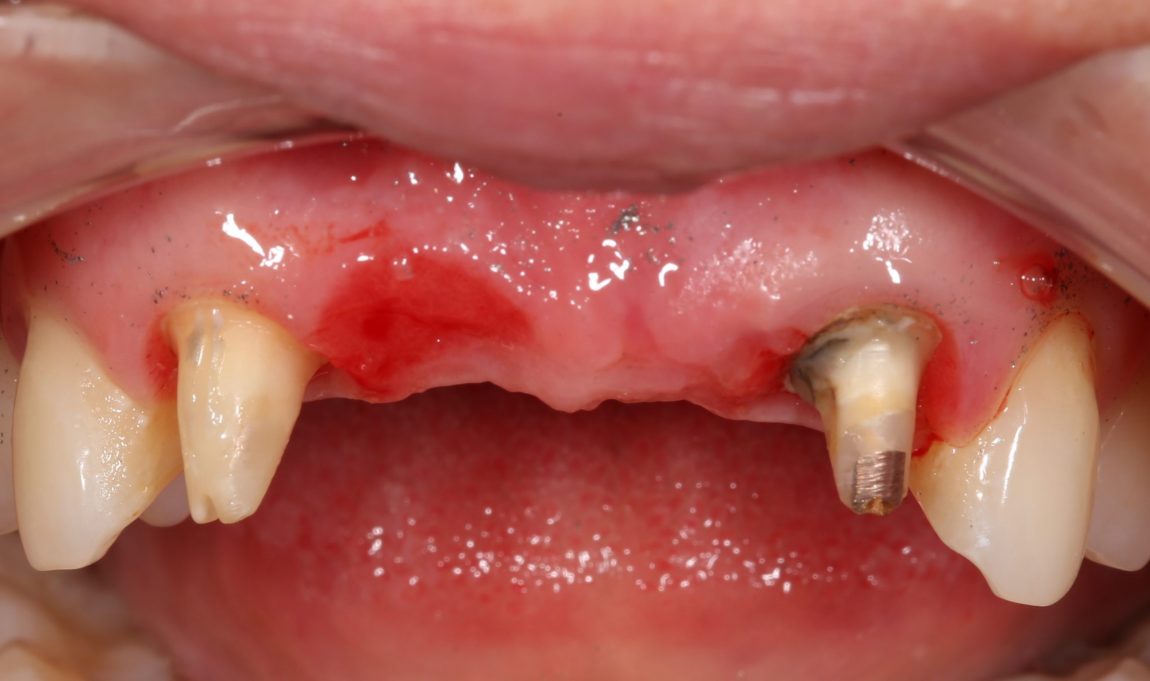

Вместо реплантаций (что легко) и реставраций (что сложнее), её тогдашний стоматолог решил решил депульпировать и обточить два боковых резца и сделать мостовидный протез. С тех пор прошло много времени, протез несколько раз меняли, а зубы перелечивали. На момент обращения к нам, верхние резцы у Татьяны выглядели следующим образом:

Пациентку беспокоили дискомфорт в области протеза, небольшая подвижность и периодическое воспаление десны в области опорных зубов.

За день до операции Давид снимает мостовидный протез:

и еще раз убеждается в том, что мы приняли правильное решение заменить опорные зубы на имплантаты:

И действительно, даже при условии качественного лечения корневых каналов, то, что осталось от боковых резцов, вряд ли можно нормально протезировать.